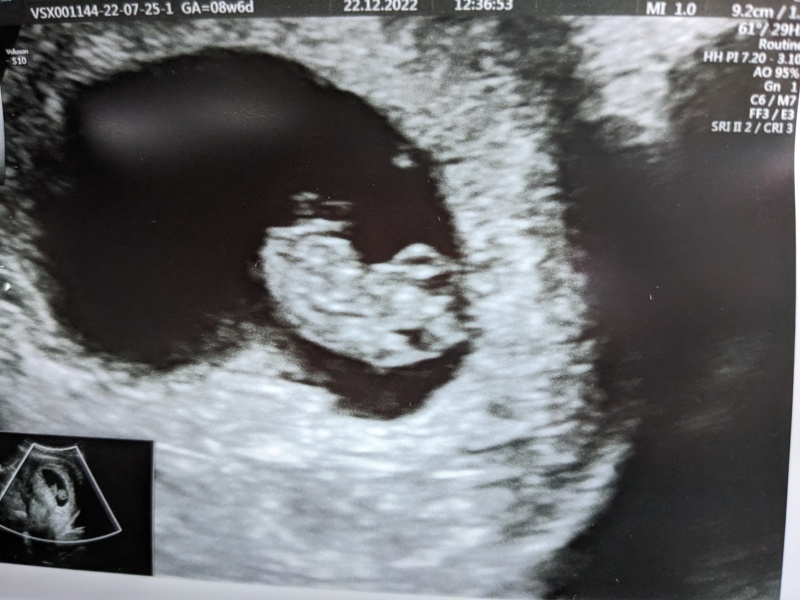

rach971 · 22/12/2022 13:03

All is well. Measured 6+6 two weeks ago at EPU and measured 8+6 today, so growing bang on. Was moving around and sucking its thumb and everything 🥹